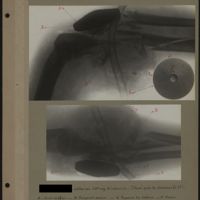

0052 - Page 48 - [Radiographie de l'épaule]0052 - Page 48 - [Radiographie de l'épaule]

0054 - Page 50 - [Radiographie de l'épaule]0054 - Page 50 - [Radiographie de l'épaule]

0059 - Page 55 - [Radiographie de l'épaule]0059 - Page 55 - [Radiographie de l'épaule]

0067 - Page 63 - [Radiographie de l'épaule]0067 - Page 63 - [Radiographie de l'épaule]

0095 - Page 91 - [Radiographies de l'épaule]0095 - Page 91 - [Radiographies de l'épaule]